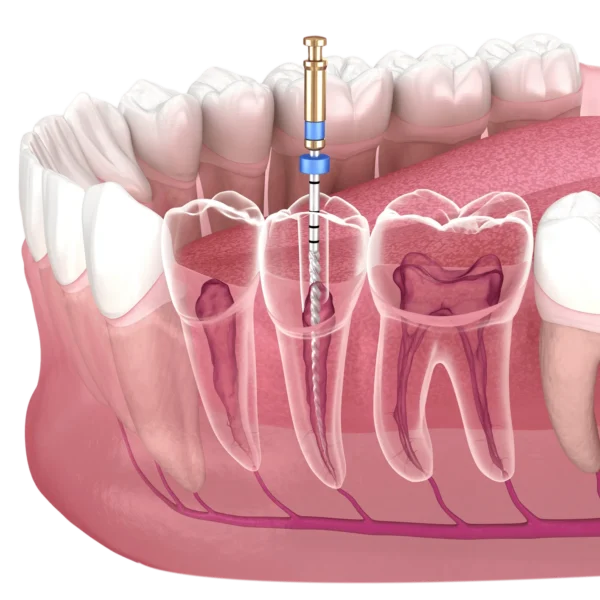

Kanal Tedavisi Nasıl Yapılır?

Kanal tedavisinde dişin üstünde delik açarak diş köküne ulaşılıp, bu bölgedeki sinir kan damarları ve dokular çıkarılarak, pulpa ve kanallar temizlenip, dezenfekte edilri ve ardından boşalan pulpa tekrar diş malzemesiyle doldurularak kaplanır.